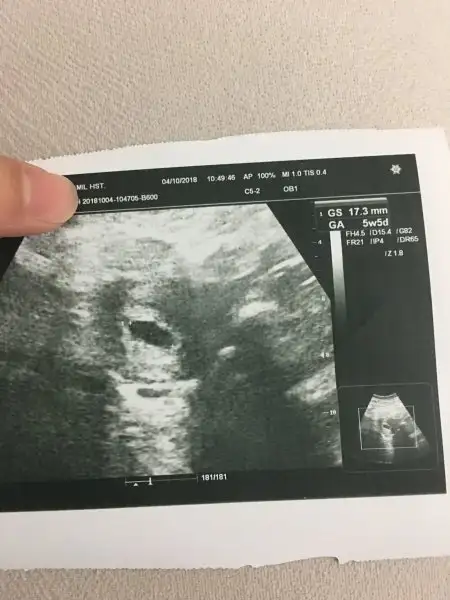

Kızlar 5. Veya 6. Hafta ultrason görüntüsü elinde olanlar ekleyebilir mi buraya çok lazımmm. Benim ki şu şekilde herşey normal mi sizce ?

Eklentiler

• image.webp